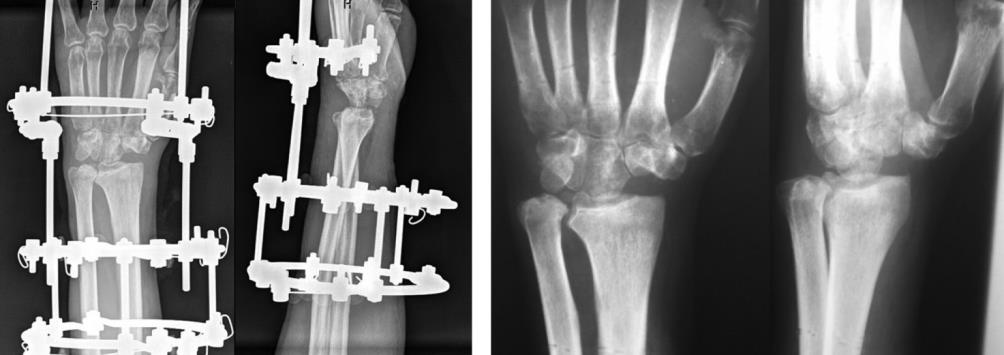

1 year after the operation, the volume of flexion and extension was 95°, of which 65° extension and 30° flexion (Fig. 6, 7).

| Fig. 5 AP and lateral radiographs taken on day 1 Fig. 6 Treatment result. AP and lateral radiographs post-surgery at 1-year follow-up |

Pain score according to VAS at rest and under loading was zero. The QuickDASH score was 13 points.

Hand grip strength was 2 points relative to a healthy hand.